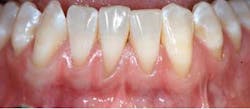

Gingival recession is defined as “the migration of the marginal soft tissue apical to the cementoenamel junction” (CEJ). Histologically, the destruction is associated with the loss of periodontal connective tissue fibers and alveolar bone, leading to exposure of the root surface to the oral environment. (3)This loss of hard- and soft-tissue-supporting structures ultimately increases the probability that patients will experience thermal or tactile sensitivity, esthetic concerns, and an increased susceptibility for root caries.

According to the proceedings from the 2014 American Academy of Periodontology Regeneration Workshop, root coverage may be attained through the application of a variety of surgical procedures. These outcomes are generally measured by reduced defect depth, gain in clinical attachment, and an increase in keratinized tissue. The associated systematic reviewprovides clear evidence that a subepithelial connective tissue graft (SCTG) procedure offers the best outcome for mean and complete root coverage, as well as an increase in keratinized tissue. (4,5) Strong evidence also supports biomaterials such as acelullar dermal matrix grafts (ADMG) or enamel matrix derivative (EMD) in conjunction with a coronally advanced flap (CAF) that can be used as an alternative to treat Miller Class I and II single-tooth gingival recession defects (figures 1 and 2). (6)Another suggestion from the proceedings was that using a split-thickness flap or tunnel technique can help to revascularize the graft by maintaining an excellent vascular supply to the flap.